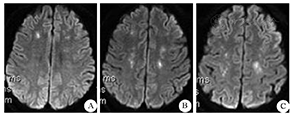

诊断依据:患者出现两项主要指标:胸闷、嗜睡,出现两项次要指标:血小板计数100×109/L,红细胞沉降率测定:1 h,33.00 mm;颅脑MRI示"双侧额叶、顶叶、胼胝体膝部急性或亚急性脑梗死",符合CFE的影像表现:T1加权像为低或等信号,T2加权像示相对对称点片状高信号,边界欠清,中脑有倒"八"病灶(图2)。

A:额叶点片状高信号;B:额叶相对对称的点片状高信号;C顶叶相对对称的点片状高信号

目前FES的诊断标准的主要指标包括:(1)皮疹瘀斑;(2)呼吸系统功能障碍;(3)神经系统功能障碍,次要指标包括:(1)心动过速;(2)体温升高;(3)血小板减少;(4)突发血红蛋白降低;(5)血沉增快;(6)尿液或血中出现脂肪滴;(7)眼底改变(脂肪滴或淤点)[11]。符合1项主要指标和3项次要指标,或2项主要指标和2项次要指标即可诊断。本例患者出现2项主要指标:呼吸系统和神经系统功能障碍,出现2个次要指标:血小板降低,红细胞沉降率升高;颅脑MRI示"双侧额叶、顶叶、胼胝体膝部急性或亚急性脑梗死",符合CFE的影像表现:T1加权像为低或等信号,T2加权像示相对对称高信号点片状病灶,边界欠清,因此该患者诊断明确,给予积极治疗后,效果明显。